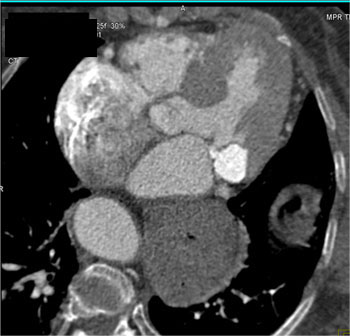

![]() | Question 3: 87 yr old female with history of hypertension had negative stress echo, presents with acute chest pain. What’s the diagnosis? |